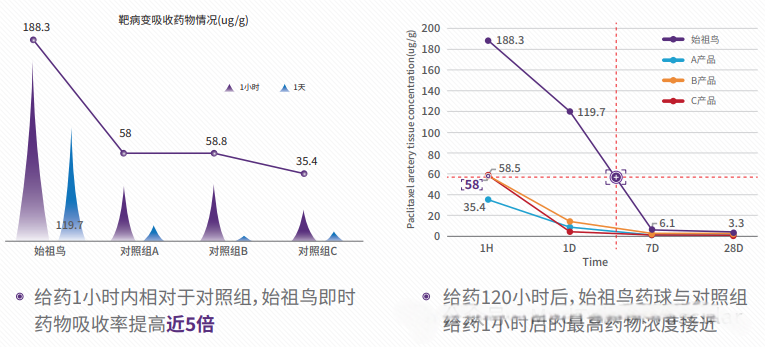

3)创新的赋形剂:DCB释放后快速激活,实现药物高效转载,药物瞬时转载量为普通DCB的3-5倍;高转载重要的点除了1h后的靶病变药物留存量是现有药球3-5倍以外,还有一个重要的时间点是在术后24h后,在靶病变处的药物浓度是现有药球的10倍左右,这个时间点正是内膜细胞开始增生的时候,可以更加有效的阻止内膜增生的进程,以达到更好的治疗效果;

图3;靶病变药物吸收情况